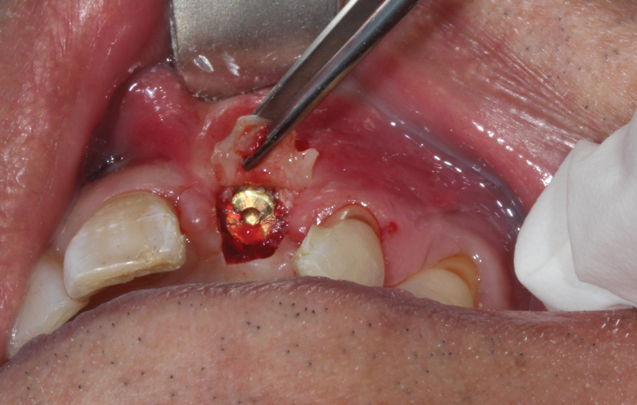

(46.) Occlusal view of the implant after placement.

Figure 46

(47.) The primary stability of the implant was confirmed to be sufficient for immediate loading.

Figure 47